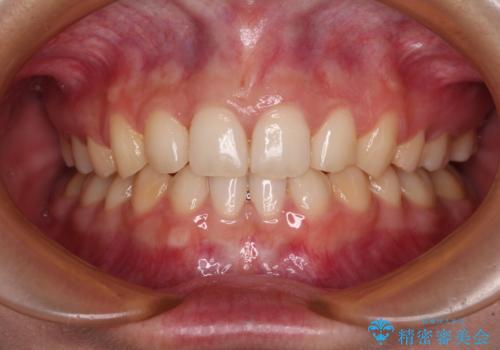

通常の抜歯矯正と抜くべき歯の位置が異なるため、咬みにくさが残ってしまうのではないかと懸念されましたが、咬み合わせに違和感なく、スムーズに治療を終えることができました。